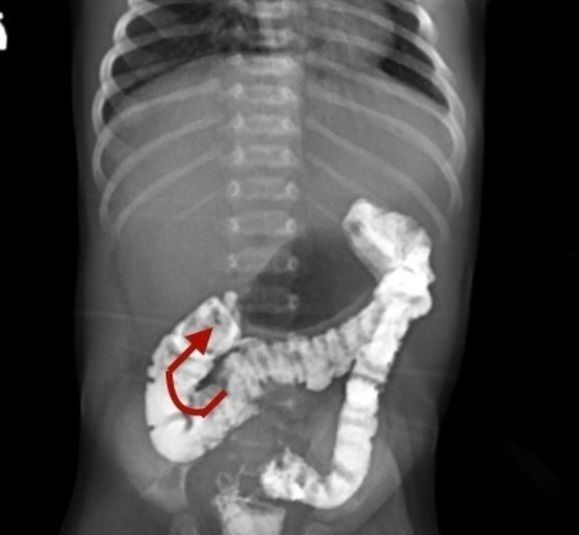

В апреле к медикам поступила новорождённая девочка с признаками непроходимости двенадцатиперстной кишки (ДПК). Малышка не могла есть, её постоянно тошнило. Врачи провели исследования и нашли у ребёнка нарушение поворота кишечника (врождённая аномалия. Неправильное положение структур кишечника в брюшной полости. — Прим. «Ё!»).

Специалисты выяснили, что толстая кишка юной пациентки находилась в неправильном положении, слепая кишка с аппендиксом располагалась под печенью. Также врачи обнаружили признаки непроходимости пилорического отдела — зоны перехода желудка в ДПК.